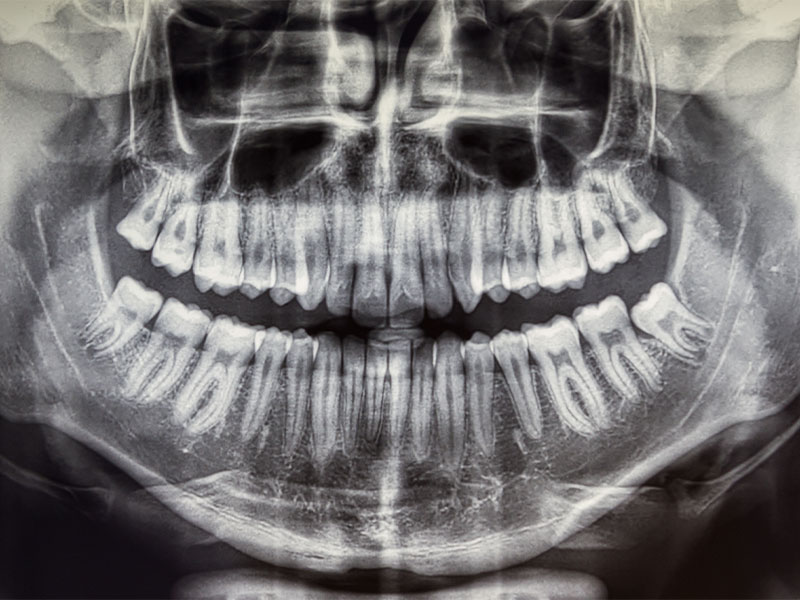

RX digitale: Diagnosi di Precisione

Le radiografie digitali sono uno strumento essenziale per una diagnosi accurata. Presso Oralise, utilizziamo sia le radiografie digitali per ottenere immagini dettagliate del cavo orale. Le rx digitale forniscono immagini bidimensionali dei denti e delle ossa mascellari.